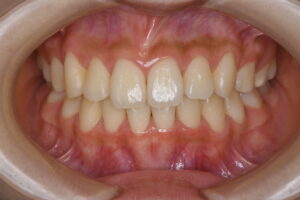

実際の症例紹介(20代女性/裏側ワイヤー矯正)

治療前

治療後

・主訴:八重歯と前歯の突出

・治療法:裏側からのワイヤー矯正(リンガル)

・治療期間:約1年半〜2年(目安)

・予想される副作用・リスク:装置装着後の違和感・疼痛、発音のしづらさ、一時的な咀嚼効率低下、ブラッシング不良によるむし歯・歯周病リスク など

※写真は代表的な症例です。口腔内の状態により治療法や期間は異なります。詳細は初診相談でご説明します。